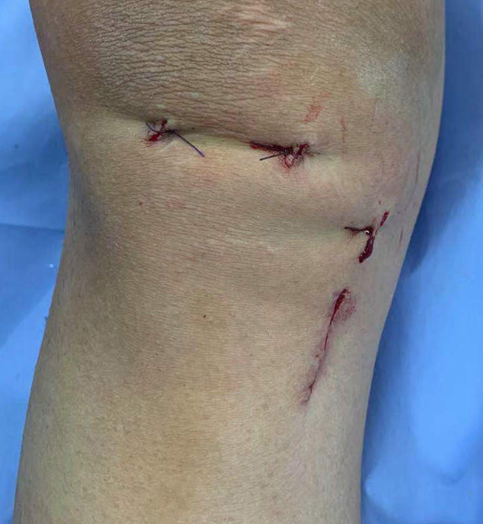

李寬新主任、張衡博士進(jìn)行了詳細(xì)的術(shù)前設(shè)計(jì),在膝關(guān)節(jié)磁共振上測(cè)量前交叉韌帶脛骨止點(diǎn)大小,在B超上評(píng)估半腱肌腱、股薄肌腱的粗細(xì),確定股骨、脛骨隧道的最佳解剖位置。2020年12月22日李寬新主任、張衡博士共同為患者實(shí)施關(guān)節(jié)鏡下自體Hamstring肌腱前交叉韌帶個(gè)性化解剖重建手術(shù)。術(shù)中應(yīng)用自主研發(fā)的關(guān)節(jié)鏡下測(cè)量器測(cè)量前交叉韌帶脛骨止點(diǎn)面積,按照張衡博士改良的韌帶大小計(jì)算公式計(jì)算出需要移植的Hamstring肌腱的直徑,并采用國(guó)際流行的Three portal 和AAMP法建立股骨隧道技術(shù)實(shí)施肌腱移植。手術(shù)僅4個(gè)Mini小切口,微創(chuàng)、美觀。術(shù)后膝關(guān)節(jié)X線示:前交叉韌帶隧道方向、膝關(guān)節(jié)解剖關(guān)系良好。